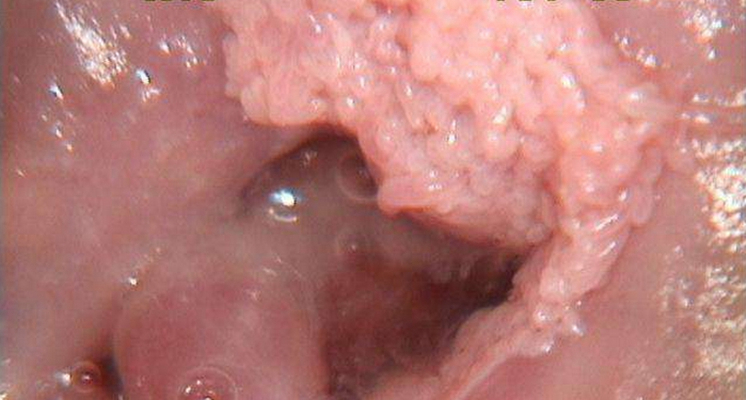

子宮頸糜爛圖片

宮頸糜爛 (8)

宮頸糜爛 (9)

宮頸糜爛 (56)

宮頸糜爛 (57)

宮頸糜爛 (58)

宮頸糜爛 (59)

宮頸糜爛 (6)

宮頸糜爛 (60)

宮頸糜爛 (7)